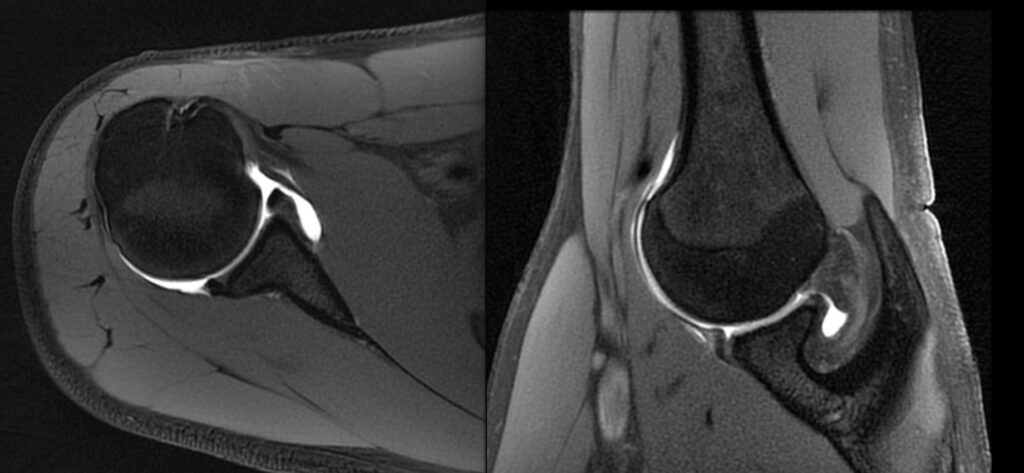

Lesioni meniscali

Anatomia I menischi sono due piccole strutture fibrocartilaginee a forma di semiluna, poste tra i condili femorali ed il piatto tibiale. Servono ad aumentare la